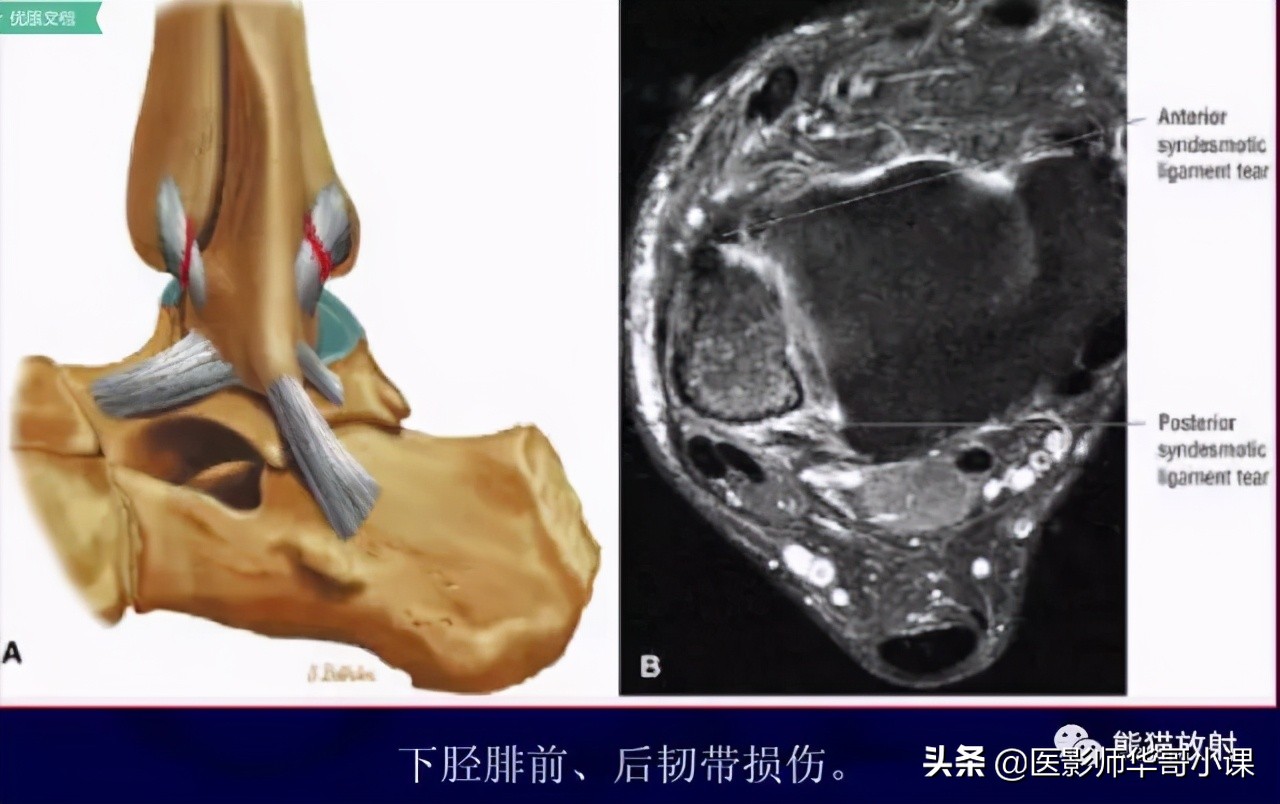

下胫腓联合韧带

胫腓骨远侧关节面由腓骨远端的凸面和胫骨远端的凹面组成,由胫腓韧带链接,关节内无软骨结构。 远端胫腓联合韧带由四部分韧带组成,包括: 骨间韧带,下胫腓前韧带,下胫腓后韧带,下横韧带。

骨间韧带由骨间膜远端增厚形成。下胫腓前韧带起于胫骨结节的前外侧,止于腓骨脊的前侧。下胫腓后韧带起于胫骨脊后侧,止于外踝后缘。下横韧带组成下胫腓后韧带的下半部分,可视为下胫腓后韧带的一部分。

下胫腓前韧带(35%),下胫腓后韧带深层(33%)对踝关节稳定性作用最大,其次是骨间膜(22%)和下胫腓后韧带浅层(9%)。

下胫腓联合远端韧带结结构,包括:骨间韧带(IOL),下胫腓前韧带(AITFL),下胫腓后韧带(PITFL),下横韧带(ITL)。